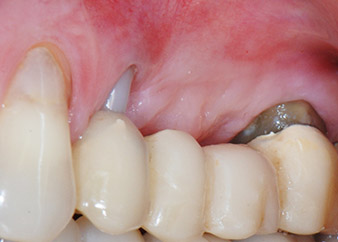

Resultado provisional a los 2 meses

Las figuras 17 y 18 muestran el resultado clínico 2 meses después de la intervención quirúrgica. La pieza 24 tenía una movilidad reducida clase I de Miller y los tejidos blandos no presentaban inflamación. Se evitó el uso de una sonda en este momento para evitar una nueva infección y para no romper la fijación epitelial. El siguiente control se planificó para el momento en el que se reanudara el tratamiento y se colocaran los pilares de cicatrización, 6 meses después de la inserción de los implantes.

Dos meses después de la intervención quirúrgica, la paciente no presentaba dolor y el área estaba libre de inflamación.

Fig. 17: Dos meses después de la intervención quirúrgica, la paciente no presentaba dolor y el área estaba libre de inflamación. Además, la pieza 24 mostraba una movilidad reducida.

después de la intervención quirúrgica

Fig. 18: Además, la pieza 24 mostraba una movilidad reducida.

Ya en la visita de los dos meses, la movilidad del “elemento dental” residual 24 se había reducido de clase II a clase I de Miller. La fijación del tejido blando se encontraba en el nivel de la pieza dental adyacente 23. Además, no se desarrollaron síntomas endodónticos ni periodontales, por lo que es posible que sea preciso reajustar el pronóstico. Sin embargo, como falta la mayor parte del hueso bucal y proximal y la acumulación de composite se extiende hasta la sección apical de la raíz, por razones biológicas, no cabe esperar un nivel de refijación más alto (Sculean et al., 2008).